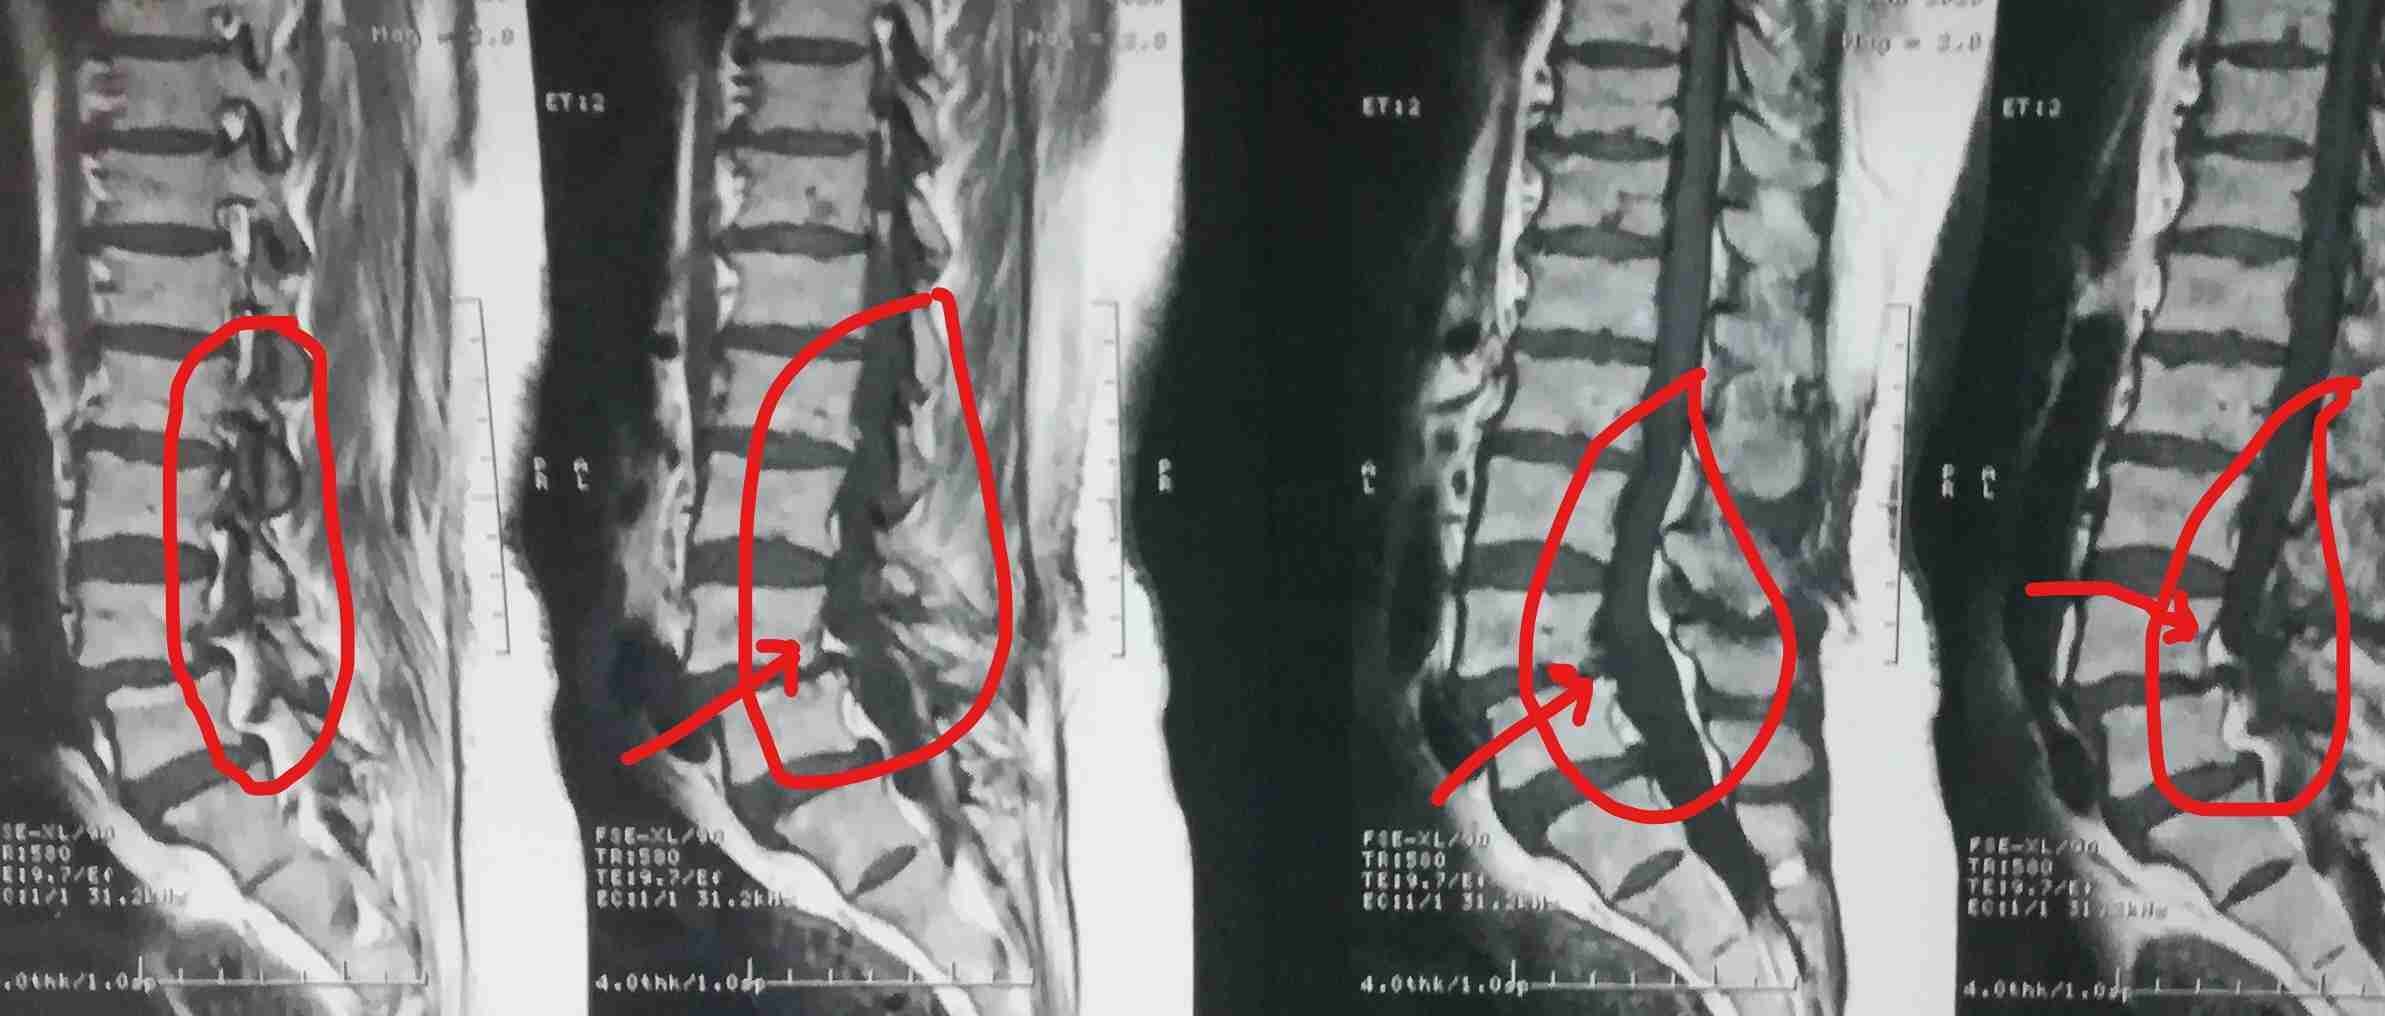

ضيق بالقناة العصبية القطنية مستويات متعددة مع تزحزح فقاري قبل وبعد الجراحة

multiple levels of lumbar nerve canal stenosis with spondylolisthesis before and after surgery

A successful surgery was performed to treat multi-level lumbar spinal stenosis accompanied by spondylolisthesis. This condition causes pressure on the nerves in the spinal column, leading to severe pain and difficulty in movement.

• Expanding the narrowed spinal canal at multiple levels

• Stabilizing the slipped vertebrae

• Relieving pressure on spinal nerves